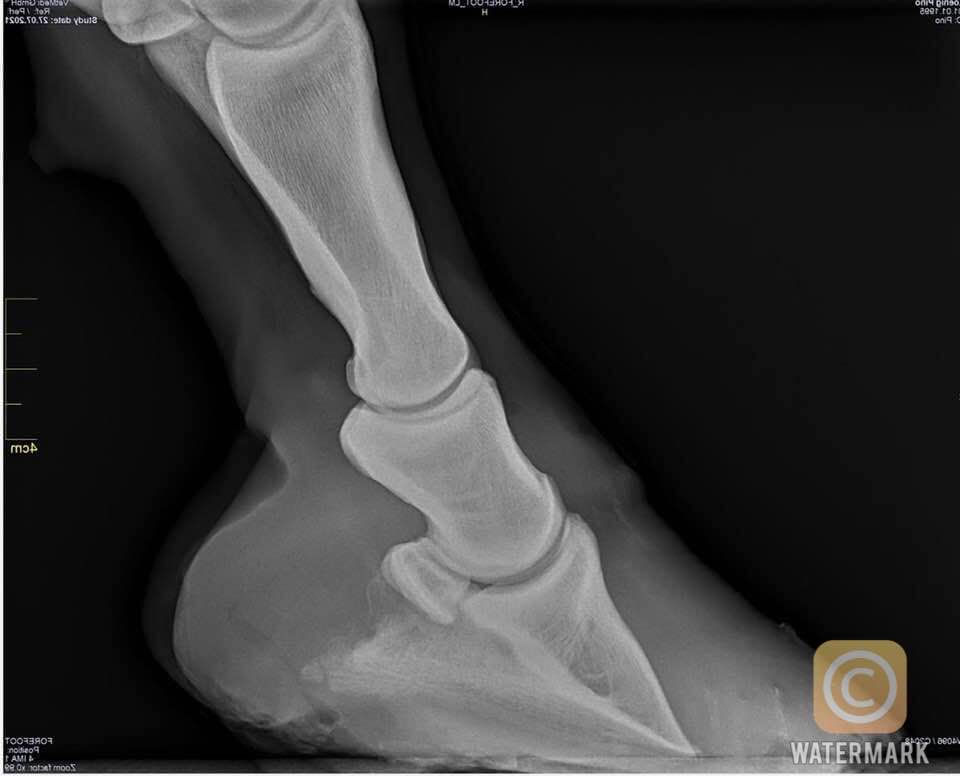

Radiographs for the Farrier Laminitis Daisy Haven Farm Can A Farrier Diagnose Laminitis By kristen kubisiak posted on september 9, 2019 | posted in lamenesses. farrier skill is critical when it comes to managing horses with laminitis —a hoof disease that causes the laminae (the. If laminitis is detected early and dealt with quickly, a favourable outcome is more likely. can a farrier cause laminitis? laminitis is diagnosed based on. Can A Farrier Diagnose Laminitis.